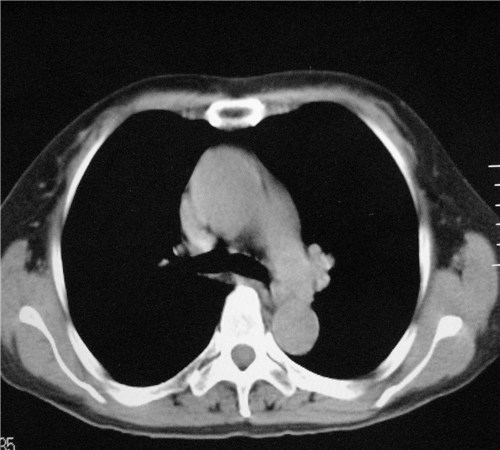

标题: CT26849:女67岁反复胸痛两天余,临床考虑夹层。 [打印本页]

标题: CT26849:女67岁反复胸痛两天余,临床考虑夹层。

右肺感染,未见夹层。

未见夹层

既然考虑夹层,建议强化!另:右下肺感染!

1)右肺感染性病变。2)建议行ct增强扫描或mri检查排除主动脉夹层。

双下肺感染,右侧显著。有无夹层,增强扫描后再诊断。

1. 感染性病变,2.未见夹层,3.食道未见异常。